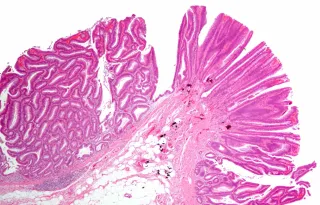

Personer som har inflammatorisk tarmsjukdom (IBD), till exempel Crohns sjukdom eller ulcerös kolit, kan få cellförändringar i tarmen som kallas dysplasi. Dysplasi är ett förstadium till cancer, och ju allvarligare dysplasin är, desto större är risken att utveckla tjocktarmscancer. Det visar en studie av forskare vid Karolinska Institutet, och NYU Grossman School of Medicine, New York, som publiceras i Clinical Gastroenterology and Hepatology.